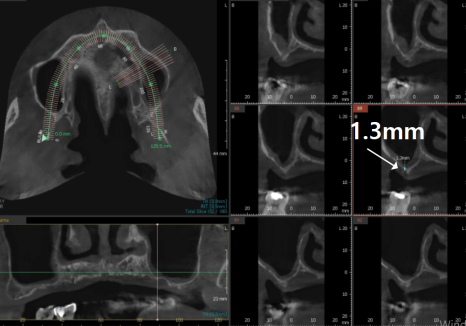

치아가 오래 없었던 분들은

뼈가 점점 얇아져

정작 임플란트를 심을 뼈는

2~3mm조차 남지 않은 경우가 많습니다.

이때 필요한 것이

바로 '상악동 거상술'입니다.

상악동 거상술은

상악동 막을 위로 들어 올려

임플란트가 들어갈 공간을 확보하는 수술입니다.

이 막은 휴지보다 얇을 정도로

매우 예민합니다.

이걸 찢지 않고 조심스럽게

들어 올린 뒤 뼈를 채워 넣어야 하죠.

집도의의 섬세한 손길이

수술의 성패를 가르는 핵심입니다.

이 환자분도 양쪽 어금니 부위

모두 상악동 거상술이 필요했습니다.